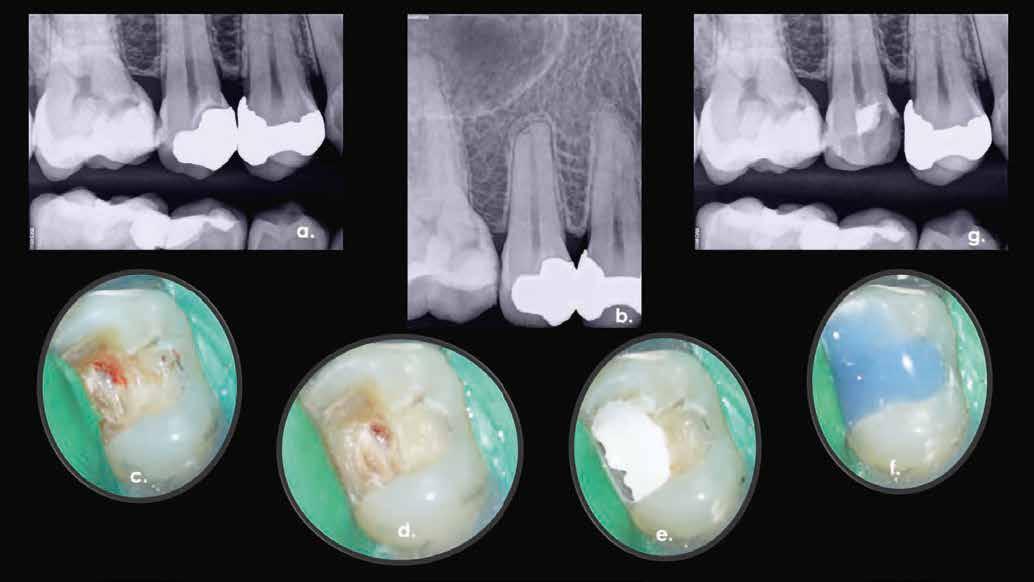

1. a–g. ábrák: A direkt pulpasapkázás lépései. Kiindulási bitewing-felvétel: A meglévő restaurátum közel helyezkedett el a pulpakamrához (a). Kiindulási periapicalis felvétel: Nincs periapicalis elváltozás fennállására utaló jel (b). A pulpaexpozíció (c). A vérzéscsillapítás céljából 20 másodpercen keresztül steril vattagombóccal történő kompressziót követően látható pulpaseb (d). A pulpasapkázás céljából behelyezett anyag, a széli részek tisztázása előtt készült felvétel (e). A röntgenárnyékot nem adó ideiglenes tömés behelyezése után készült felvétel (f). Az első ülés végén a röntgenárnyékot nem adó ideiglenes töméssel ellátott fogról készített röntgenfelvétel (g).

2. ábra: A hat hónapos kontroll alkalmával készített röntgenfelvételen vastag dentinhíd látható a pulpasapkázó anyag alatt.

3. ábra: A hároméves kontroll alkalmával készített röntgenfelvételen megfigyelhető a restaurátum pontos illeszkedése.

6. a–d. ábrák: A bal alsó második nagyőrlőfogon (3.7) kialakított konzervatív hozzáférési nyíláson keresztül végzett endodonciai kezelés lépései. A mezialis gyökér jelentős mértékben görbült. A gyökértömés hidraulikus kondenzációs technikával készült.

b. ábrák: A jobb alsó első nagyőrlőfogon (4.6) lévő cirkóniumkoronán keresztül elvégzett endodonciai kezelés. A hozzáférési nyílás kialakítása a lehető legkonzervatívabb módon történt. A gyökértömés hidraulikus kondenzációs technikával készült.

5. a–l. ábrák: Az incisális élen keresztül kialakított hozzáférés lehetővé teszi a pericervikális dentin megőrzését. Kalcifikáció esetén CBCT-felvétel készítése hasznosnak bizonyulhat a hozzáférési nyílás tervezése során (a–d) . Minden fog koronai helyreállítása a gyökértömés elkészítésével egyidejűleg történt. A négyéves (e–h) és a kétéves (i–l) kontrollok alkalmával készített röntgenfelvételeken teljes gyógyulás látható. Mindkét fog tünetmentes és funkcióképes volt. (Dr. Viraj Vora esetei)

Szuvas lézión keresztül történő hozzáférés (a). A fog koronai helyreállítása a gyökértömés elkészítésével egyidejűleg történt (b és c). (Dr. Dale Jung esete)

6. a–c. ábrák:

9. a–j. ábrák: A szuvas lézión és a meglévő restaurátumon keresztül történő mezializált és distalizált hozzáférés (a–f). A fogak restaurálása közvetlenül a gyökértömések elkészítése után történt. Az egyéves kontroll során készített röntgenfelvételen a gyógyulás jelei láthatóak, annak ellenére, hogy a gyökércsatornák feltágítása konzervatív módon történt, és a pulpakamra tetejének több mint fele megőrzésre került (g–j). (Dr. Viraj Vora esetei)

10. a–f ábrák: Kiindulási állapot (a). A hozzáférési nyílást a meglévő restaurátumon (b) keresztül alakítottuk ki, így egy bukkális irányba néző üreg jött létre (c-d). A fogról készült röntgenfelvétel. A fog restaurálása közvetlenül a gyökértömés elkészítése után történt (e). Az egyéves kontroll során készített röntgenfelvételen a gyógyulás jelei láthatóak. A páciens panaszmentes volt, a fog pedig mindvégig funkcióban volt tartva (f). (Dr. Dale Jung esete)

11. a–f ábrák: Kiindulási állapot: röntgenfelvétel (a); intraorális fotó (b). A hozzáférési nyílás a szuvas lézión keresztül került kialakításra, így egy linguális irányba néző üreg jött létre (c). A bukkális csatornák feltárása érdekében az okkluzális felszínen egy különálló apró nyílás is kialakításra került (d). A pulpakamra teteje alatti terület meghajlított eszközök segítségével végeztük (e). A fogról készült röntgenfelvétel. A fog koronai helyreállítása a gyökértömés elkészítésével egyidejűleg történt (f). (Dr. Dale Jung esete)

12. a–e ábrák: A koronával ellátott felső kisőrlőfog trepanálása során tölcsérszerűen szűkülő hozzáférési nyílás került kialakításra (stepped access), (a-b). A restaurátum anyagában szélesebb feltárást végeztünk, míg a saját foganyagot konzervatív módon távolítottuk el (c). A bukkállis csatorna feltárását követően az üreget óvatosan kiterjesztettük palatinális irányba (cd). A fogról készült röntgenfelvétel. A trepanációs üreg végleges zárása a gyökértömés elkészítésével egyidejűleg történt (e). (Dr. Bobby Nadeau esete)

13. a–d ábrák: Tölcsérszerűen szűkülő hozzáférési nyílás: a restaurátum anyagán belül szélesebb feltárás történt, egészen a foganyag eléréséig. A pulpaűr megnyitása konzervatív módon, a várható elhelyezkedésének megfelelő pozícióban történt (a–c). A fogról készült röntgenfelvétel. A fog koronai helyreállítása a gyökértömés elkészítésével egyidejűleg történt (d). (Dr. Dale Jung esete)

38 e-Journal ENDODONTIA

15. a–f. ábrák: A nagy kiterjedésű direkt restaurátummal ellátott felső nagyőrlő fogban tölcsérszerűen szűkülő hozzáférési nyílás került kialakításra (a-b). A restaurátum anyagának széles feltárása biztosította az akadálytalan hozzáférést a dentinhez (c-d). A fogról készült röntgenfelvétel. A fog koronai helyreállítása a gyökértömés elkészítésével egyidejűleg történt (e). A kétéves kontroll során készült röntgenfelvételen a gyógyulás jelei láthatóak. A páciens panaszmentes, a fog funkcióképes volt (f). (Dr. Viraj Vora esete)

16. a–d ábrák: A széles pulpakamrákkal rendelkező fogak esetében dentinhíd megtartásával járó hozzáférési nyílás (dual-entry truss access) kialakítását javasoljuk (piros nyíl; a). A meziális csatornák feltárása a meziális lézión keresztül, a disztális csatornák feltárása pedig külön üregből történt (b). A dentinhíd (fekete nyilak; c-d) megtartása feltehetően hozzájárul a fog szerkezeti integritásának megőrzéséhez. A fog koronai helyreállítása a gyökértömés elkészítésével egyidejűleg történt. (Dr. Dale Jung esete)

17. a–f ábrák: Széles platformmal rendelkező alsó moláris fog (zöld nyíl; a és b). Először az okkluzálisan elhelyezkedő restaurátum került eltávolításra (c). Ezt követően végeztük el a nagyobb átmérővel rendelkező disztális csatornabemenet feltárását (piros nyíl; d). A meziális csatornák felkutatása a kiindulási röntgenfelvételen végzett hozzávetőleges mérési eredmények alapján történt (fekete nyilak; e). A dentinhíd megtartásával tovább tudtuk növelni a fog szerkezeti integritását (kék nyíl). A fogról készült röntgenfelvétel. A fog koronai helyreállítása a gyökértömés elkészítésével egyidejűleg történt (f). (Dr. Bobby Nadeau esete)